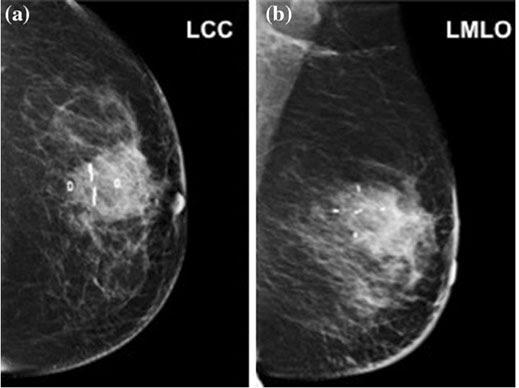

The BioZorb implant can be seen within a breast in these two mammogram images from different angles.

The implantable marker consists of a framework made of a bioabsorbable material that holds six titanium clips. The framework slowly dissolves in the body over the course of a year or more. The tiny marker clips stay in place so the surgical site can be viewed for long-term monitoring such as mammograms.